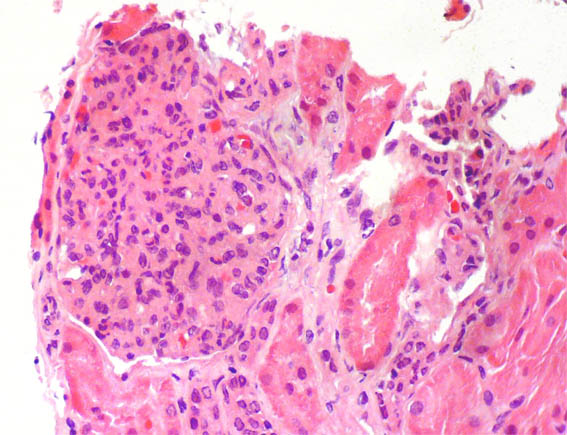

Figura 1.

H&E, X400.